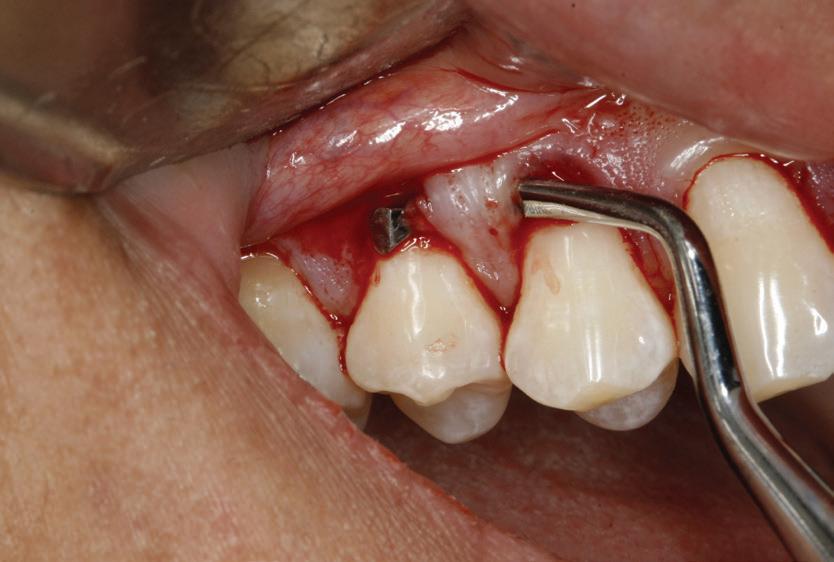

Planul de tratament a început cu accent pe restabilirea sănătății parodontale. Într-o ședință ulterioară, odată cu îmbunătățirea stării parodonțiului, s-a efectuat restaurarea molarului nr. 46. Sub anestezie la Spina Spix pe partea dreaptă și

Figurile:

1. Situația clinică inițială.

2. Radiografia inițială.

3. Cavitate de clasa a II-a preparată.

4. Septomatrix pe poziție.

5. Cavitatea profundă.

izolarea cu digă de cauciuc, restaurarea din amalgam a fost îndepărtată complet și s-a obținut accesul la cavitatea carioasă (fig. 3-5). În ciuda proximității față de țesutul pulpar, nu a avut loc nicio expunere, iar cavitatea de clasa a II-a a fost restaurată complet cu Biodentine™ (fig. 6-8).